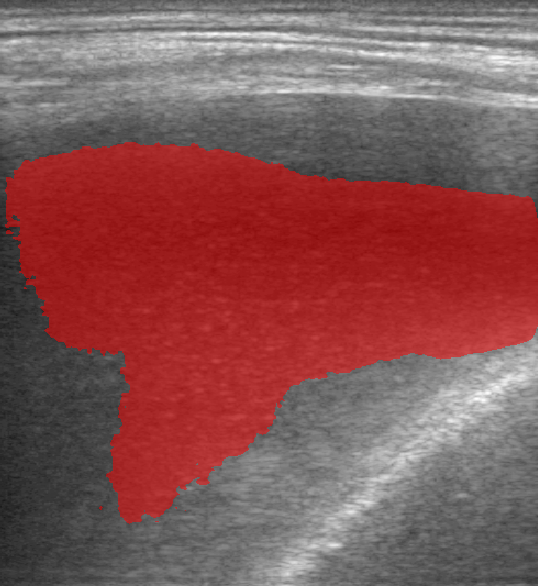

A total of 143 images were acquired from 59 patients. The images were obtained at the left and right PLAPS (PosteroLateral Alveolar and/or Pleural Syndrome) and subcostal views [4] with linear array and curved array (abdominal) ultrasound probes. The data were split according to the use of these probes into two datasets of 51 and 92 images, respectively for linear array and curved array. We denote these datasets as Dataset A (linear array) and Dataset B (curved array). All images were annotated at the time of acquisition to measure the extent of the effusion. These annotations consisted of small crosses at the top and bottom of the deepest area of effusion. See Figure 1 (left column) for example images.

Before being used for training and evaluating the models, each image was automatically cropped using a rectangular/cone mask to remove non-imaging content. Next, we applied an inpainting text algorithm using keras-ocr followed by template matching and edge detection algorithms from opencv to remove the annotations that were added to the images to measure the effusion. Examples of the outputs of this preprocessing are shown in Figure 1 (centre column).

All images in both datasets were manually segmented using the ITK-SNAP software [14] (www.itksnap.org) by a trained observer. Examples of ground truth segmentations are shown in Figure 1 (right column). These segmentations acted as ground truths for training and evaluating the proposed models. Additionally, a second trained observer performed independent segmentations of subsets of 10 random images each from the two datasets. These were used to compute an estimate of inter-observer variability in the manual segmentation process.

Rows 1-2: Dataset A. Rows 3-4: Dataset B.